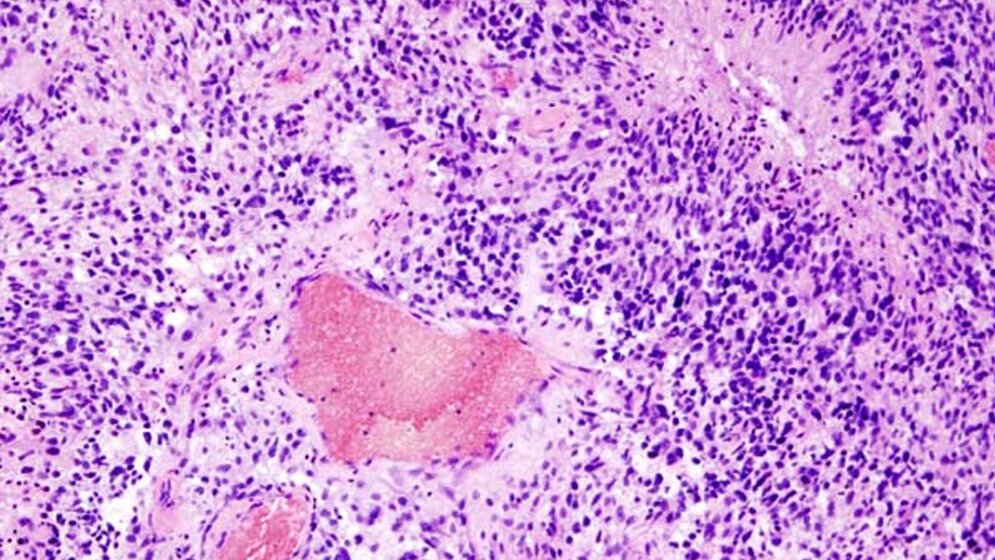

Die genetische Ausstattung eines Hirntumors kann die Überlebenszeit der Betroffenen erheblich beeinflussen. Ein Beispiel liefert ein Gen, das für die Aktivität des Enzyms Isocitrat-Dehydrogenase (IDH) verantwortlich ist. Ist es etwa bei Gliomen – eine bestimmte Art von Hirntumor – mutiert, so haben die Betroffenen eine deutlich bessere Prognose als bei unverändertem IDH-Gen.

Um die molekulargenetischen Eigenschaften eines Tumors zu charakterisieren, müssen Ärzte dem Patienten eine Gewebeprobe entnehmen, also eine Biopsie oder Operation durchführen. Von der genetischen Ausstattung eines Tumors kann dann auch abhängen, welche Behandlungsschritte – vor allem Strahlen- und Chemotherapie – ergänzt werden müssen.

Die Wissenschaftler haben computergestützt spezielle Merkmale von Bildern bestimmt, die mittels PET unter Verwendung der in Jülich entwickelten radioaktiv markierten Aminosäure O-(2-[18F]fluoroethyl)-L-tyrosin (FET) entstanden waren. Insbesondere haben sie dabei sogenannte Texturmerkmale berechnet. Diese Merkmale beschreiben, wie unregelmäßig die FET-Anreicherung im Tumor ist. "Die Grundidee stammt aus der automatischen Auswertung von Satellitenbildern. Computerprogramme erkennen dort anhand von Strukturmerkmalen zum Beispiel, wo sich ein See oder eine Stadt befindet", erläutert Philipp Lohmann.

Im nächsten Schritt trainierten die Wissenschaftler eine lernende Software darin, aus den Texturmerkmalen und anderen FET PET-Parametern zu schließen, ob der Tumor eine IDH-Mutation aufweist oder nicht. Sie gaben dabei der Software stets Rückmeldung, inwieweit das Ergebnis mit den Biopsie-Ergebnissen übereinstimmte. Die lernende Software passte daraufhin ihr mathematisches Modell an. Am Ende unterschied sie auf Basis der Bilder mit einer Genauigkeit von rund 93 Prozent zwischen Tumoren mit und ohne IDH-Mutation.